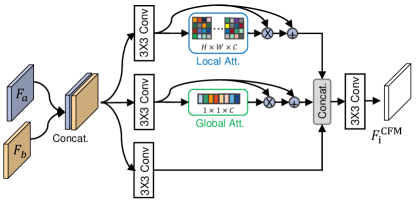

3.4 Cross-level Fusion Module

We propose the CFM to fuse the features from adjacent levels, which can effectively exploit cross-level contextual semantics to improve the polyp segmentation performance. Specifically, taking and as examples, they are first concatenated to obtain the fused feature . Then, is passed through three sequential convolution operations, and we obtain , , and . Because local contexts can avoid small polyps being ignored, while global contexts are helpful to emphasize feature learning to locate some large polyps. Therefore, in the proposed CFM, we present to capture local contexts as well as exploit global contexts to enhance feature representations. To achieve this, in the “Local Att.” branch shown in Fig. 3, we conduct two point-wise convolutions (PWC) dai2021attentional to learn the local attentional weights. Besides, in the “Global Att.” branch shown in Fig. 3, we first carry out a global average pooling (GAP) operation and then utilize PWC operation to learn the global weights. Therefore, we can obtain the local and global attention-based weights as follows:

where denotes the point-wise convolution, and the kernel sizes of and are and , respectively. Here is a channel reduction ratio, and is the channel size. Besides, and indicate the Sigmoid and ReLU activation functions, respectively. Next, we conduct the element-wise multiplication between the features and the corresponding weights with residual connection, thus the enhanced features can be given by

where denotes element-wise multiplication. After that, the two attention-enhanced features and the original feature are concatenated and then fed to a sequential convolution operation to generate the final output , which is obtained as follows:

| (6) |